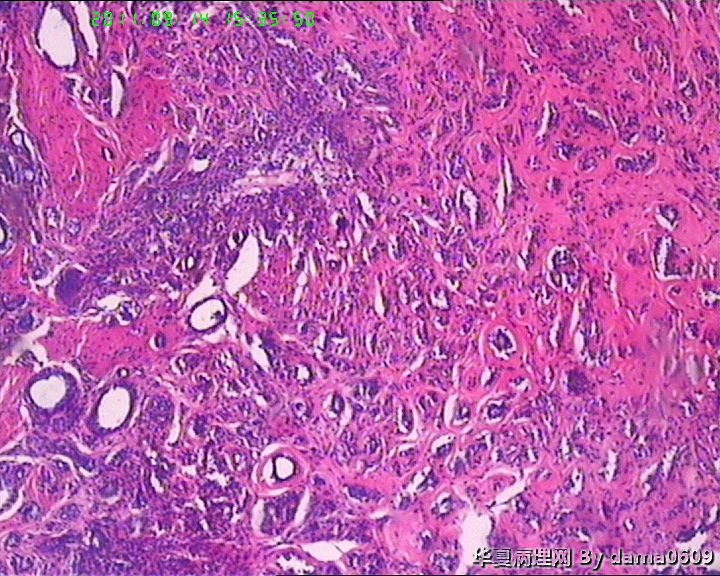

女,22岁,乳腺肿物,病史不详。

不整形软组织肿物一个,V:2.0x1.5x1.5cm。无包膜。切面实性,灰白色,小结节状,质中。

镜下结构复杂,图3、4、8、10、11、12、13、15、17、18、19、20为肿物中央区域,占标本大部分,图1、2、7、14为肿物边缘部分,图5、6、9、16、21为二者交界处。有点乱,不好意思,请老师别介意。

请教老师,诊断:硬化性腺病,可以吗??谢谢!!

• 乳腺肿物,急于求教!!图4

图4

会诊结果::(乳腺)腺管腺病,伴纤维腺瘤形成。

该例患者经上级医院会诊,回报:(乳腺)腺管腺病,伴纤维腺瘤形成。